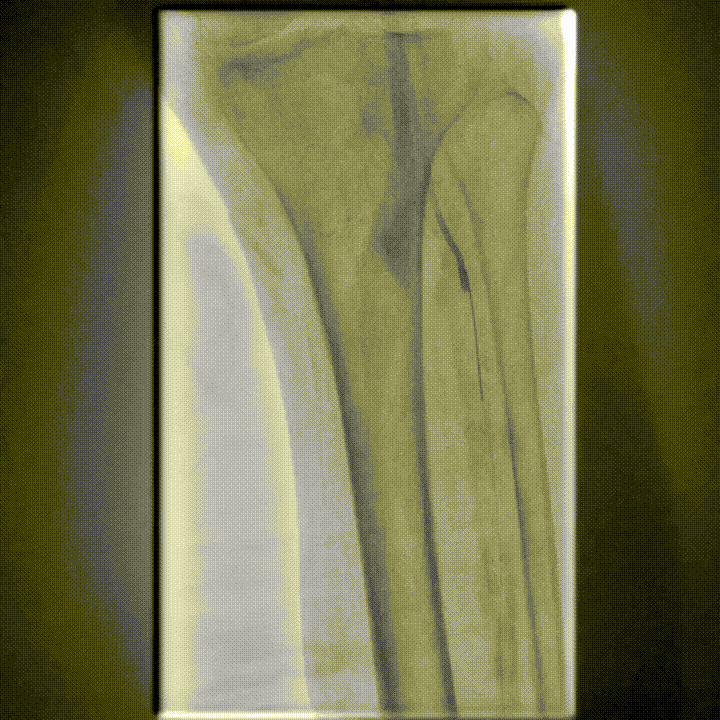

图为:药涂球囊扩张图为:药涂球囊扩张

图为:支架植入

图为:术后造影